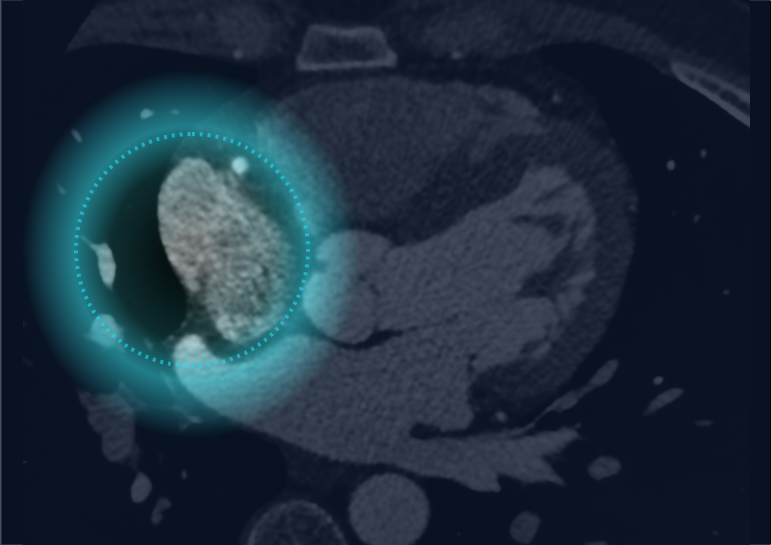

Automated Cardiac Image Analysis and Interpretation

Dyad Medical Inc. |